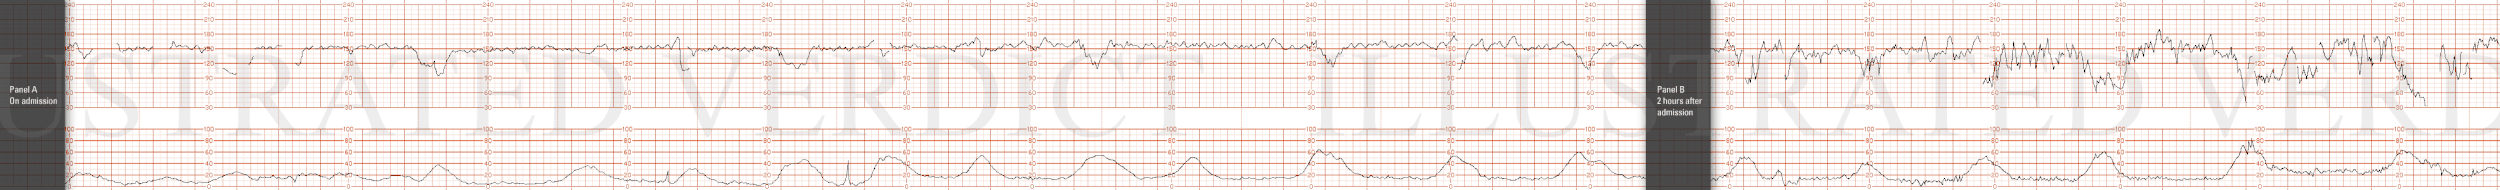

STRIP 69

1. Panel 20 minutes

Nine contractions, each 50-60 sec long, in last 20 minutes. 2nd, 3rd and 4th contraction to long, about 10 secs, 6th needs 15 secs off,

Baseline rate at +/- 150 bpm over 20 minute panel with minimal variability

Three mild-moderate variable decelerations - (varying in duration from20-35 sec each to nadir varying between 105 to 120 bpm ( 4, 10 (needs to be moved over 1 min) and 16 (move 30 secs over to right) minutes in the 20 minute segment). There is no progression in depth or duration of the decelerations - random

There is one 18-bpm acceleration at minute 8-9 in the last 20 minutes

Category 2 with mild to moderate variable decelerations and minimal variability.

1. 1st panel:

Tracing to show 140 bpm with average variability and no decelerations. Five 50-second contractions noted in 20 minutes of observation. (1st and 2nd contraction 10sec less, 5th 30secs less

2nd panel:

Panel: 20-minute of FHR strip.

Contractions:11 in 20 minutes, each lasting +/- 50-55 seconds. (1st 3rd, 4th, 6th, 7th, 8th, 10th and 11th too long 10-15 secs off)

Baseline +/- 165 bpm with minimal variability

Four mild to moderate, (but not unusual variable decelerations down to range of 105 to 125 bpm at minute 4, 11, 17 minutes, each with duration varying between 25-35 seconds.- with prompt return to baseline. There is no progression in depth or duration of decelerations – random. (1st 2nd more abrupt, 1st deeper, 4th more abrupt and deeper)

There are no spontaneous accelerations.

Indicate scalp stimulation at minute 18 with no resultant acceleration